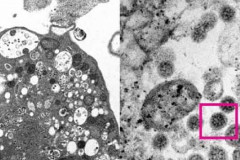

Գիտնականների նոր մշակումը կարող է արդյունավետ լինել կորոնավիրուսի դեմ Ռուս սակրավորները ոչնչացրել են Ասկերանի շրջանում բնակչի կողմից հայտնաբերված ռեակ... Մեկ օրում բացահայտվել է 62 հանցագործություն Հակառակորդի կրակոցից ժամկետային երեք զինծառայողի սպանության դեպքի առթիվ հարուցվե... Հայաստանում հաստատվել է կորոնավիրուսով վարակվելու 289, մահվան՝ 4 նոր դեպք Վթար՝ Երևանի Թբիլիսյան խճուղում․ կան տուժածներ (տեսանյութ) Ողջ աշխարհում կորոնավիրուսով վարակման ռեկորդային ցուցանիշ է գրանցվել անցյալ շաբա... ՀՀ տարածքում կան փակ և դժվարանցանելի ավտոճանապարհներ Ադրբեջանական ստորաբաժանումների իրականացրած սադրանքից հետո կեսգիշերին հայտնաբերվե... Լույս չի լինելու Ժամեր առաջ սպանված 20-ամյա Ռուդն էր սա գրել դեռ նոյեմբերի 10-ին՝ կապիտուլյացիայ... «Եթե այսպես շարունակվի` ամռանն էլ թշնամին կգա Սևանում կլողանա, մեր իշխանությունն... Նրա փոխարեն այդ դիրքում պետք է լինեին թրքասեր, ադրբեջանի հետ խաղաղության դարաշրջ... Ծանոթ ու միարժամանակ անհայտ … լվացքի փոշի Հայկական կողմն ունի 2 զոհ, իրադրությունը սահմանին հարաբերականորեն կայուն է․ ՊՆ Ադրբեջանական կողմը հաղորդել է մեկ զոհի մասին Ունենք զոհեր, վիրավորներ, կրակոցները շարունակվում են. Գեղամասար համայնքի ղեկավար... Գյուղում կրակոցները լսվում են, դիրքերում վիրավորներ ունենք. hիմա էլ լարված իրավի... Եղանակը Հայաստանում Գիտնականը պատմել է «օմիկրոն»-ի նկատմամբ իմունային համակարգի խոցելիության մասին Հակառակորդն օգտագործում է հրետանային միջոցներ և ԱԹՍ-ներ. ունենք 3 վիրավոր Ասրյան. ՀԱՊԿ հայ խաղաղապահներին Ղազախստան տանելը ճիշտ որոշում է Ադրբեջանի ԶՈՒ ստորաբաժանումները կրակ են բացել Վերին Շորժայի հատվածում տեղակայված... Եվրոպայի բնակչության կեսից ավելին առաջիկա 6-8 շաբաթում կվարակվի «Օմիկրոնով». ԱՀԿ Եղանակը՝ առաջիկա օրերին Եվրոպական գործակալությունը դրական է գնահատել «Սպուտնիկ V» պատվաստանյութի կլինիկա... Կրակոցներ Սյունիքի մարզում. Գորիսում ինքնաձիգով կրակոցներ են արձակել BMW-ի վրա Խոշոր ավտովթար Վայոց Ձորում Հայաստանում հաստատվել է կորոնավիրուսով վարակվելու 243, մահվան՝ 2 նոր դեպք ՀՀ տարածքում կան փակ և դժվարանցանելի ավտոճանապարհներ